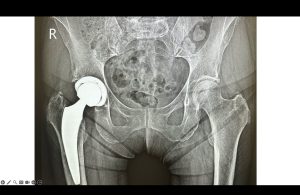

Protesi dell’anca con accesso mini invasivo anteriore immagine radiografica

Mk Medical Poliambulatorio Roma

Indicazioni, risparmio osseo e durata della protesi

Il risparmio osseo è un vantaggio chiave nei pazienti più giovani, poiché facilita eventuali revisioni. La durata media delle componenti protesiche è in genere 15–20 anni e non dipende dall’accesso chirurgico, ma dalla morfologia dell’anca usurata e dalla tipologia di protesi selezionata.